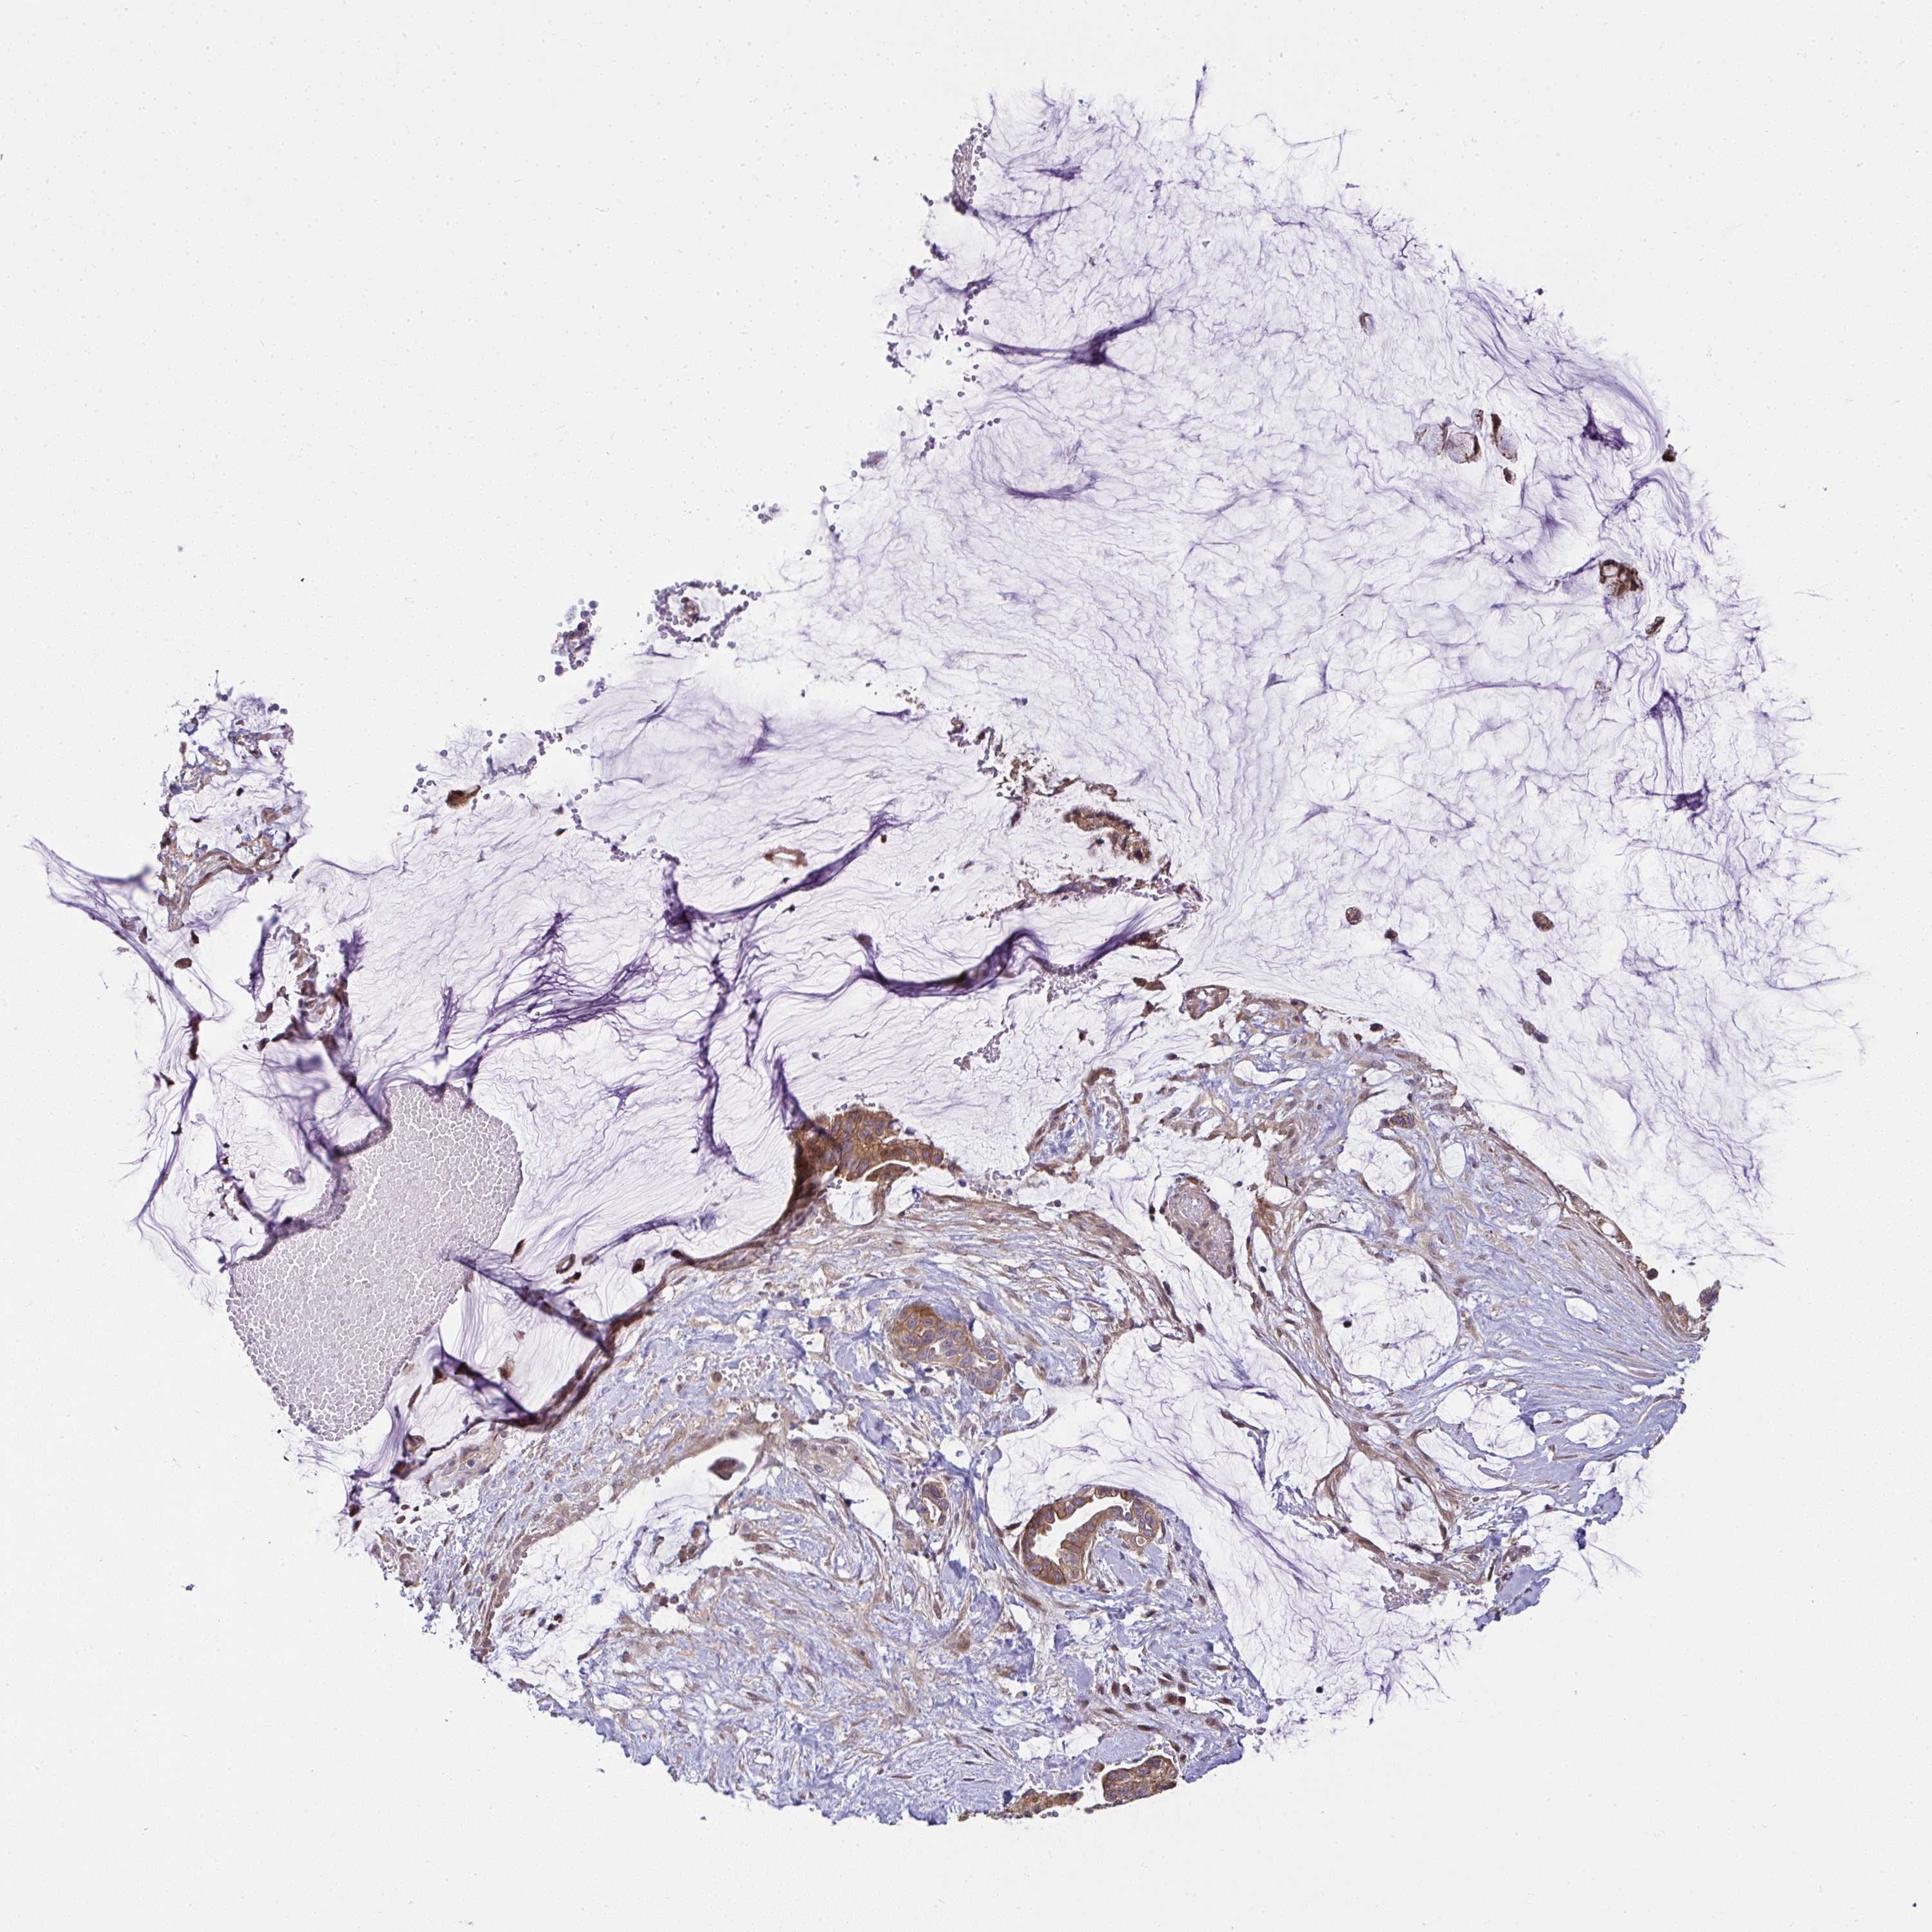

OVARIAN CANCER - Protein expressioni

A mouse-over function shows sample information and annotation data. Click on an image to view it in a full screen mode. Samples can be filtered based on level of antibody staining by selecting one or several of the following categories: high, medium, low and not detected. The assay and annotation is described here.

Note that samples used for immunohistochemistry by the Human Protein Atlas do not correspond to samples in the TCGA dataset.

Antibody stainingi

Antibody staining in the annotated cell types in the current human tissue is reported as not detected, low, medium, or high, based on conventional immunohistochemistry profiling in selected tissues. This score is based on the combination of the staining intensity and fraction of stained cells.

Each image is clickable and will lead to virtual microscopy that enables deeper exploration of all samples and also displays staining intensity scores, fraction scores and subcellular localization as well as patient and tissue information for each sample.

Antibody HPA056686

Staining

High

Medium

Low

Not detected

Intensity

Strong

Moderate

Weak

Negative

Quantity

>75%

75%-25%

<25%

None

Location

Nuclear

Cytoplasmic/membranous

Cytoplasmic/membranous,nuclear

Cystadenocarcinoma, serous, NOS

Carcinoma, endometroid

Cystadenocarcinoma, mucinous, NOS

Carcinoma, NOS